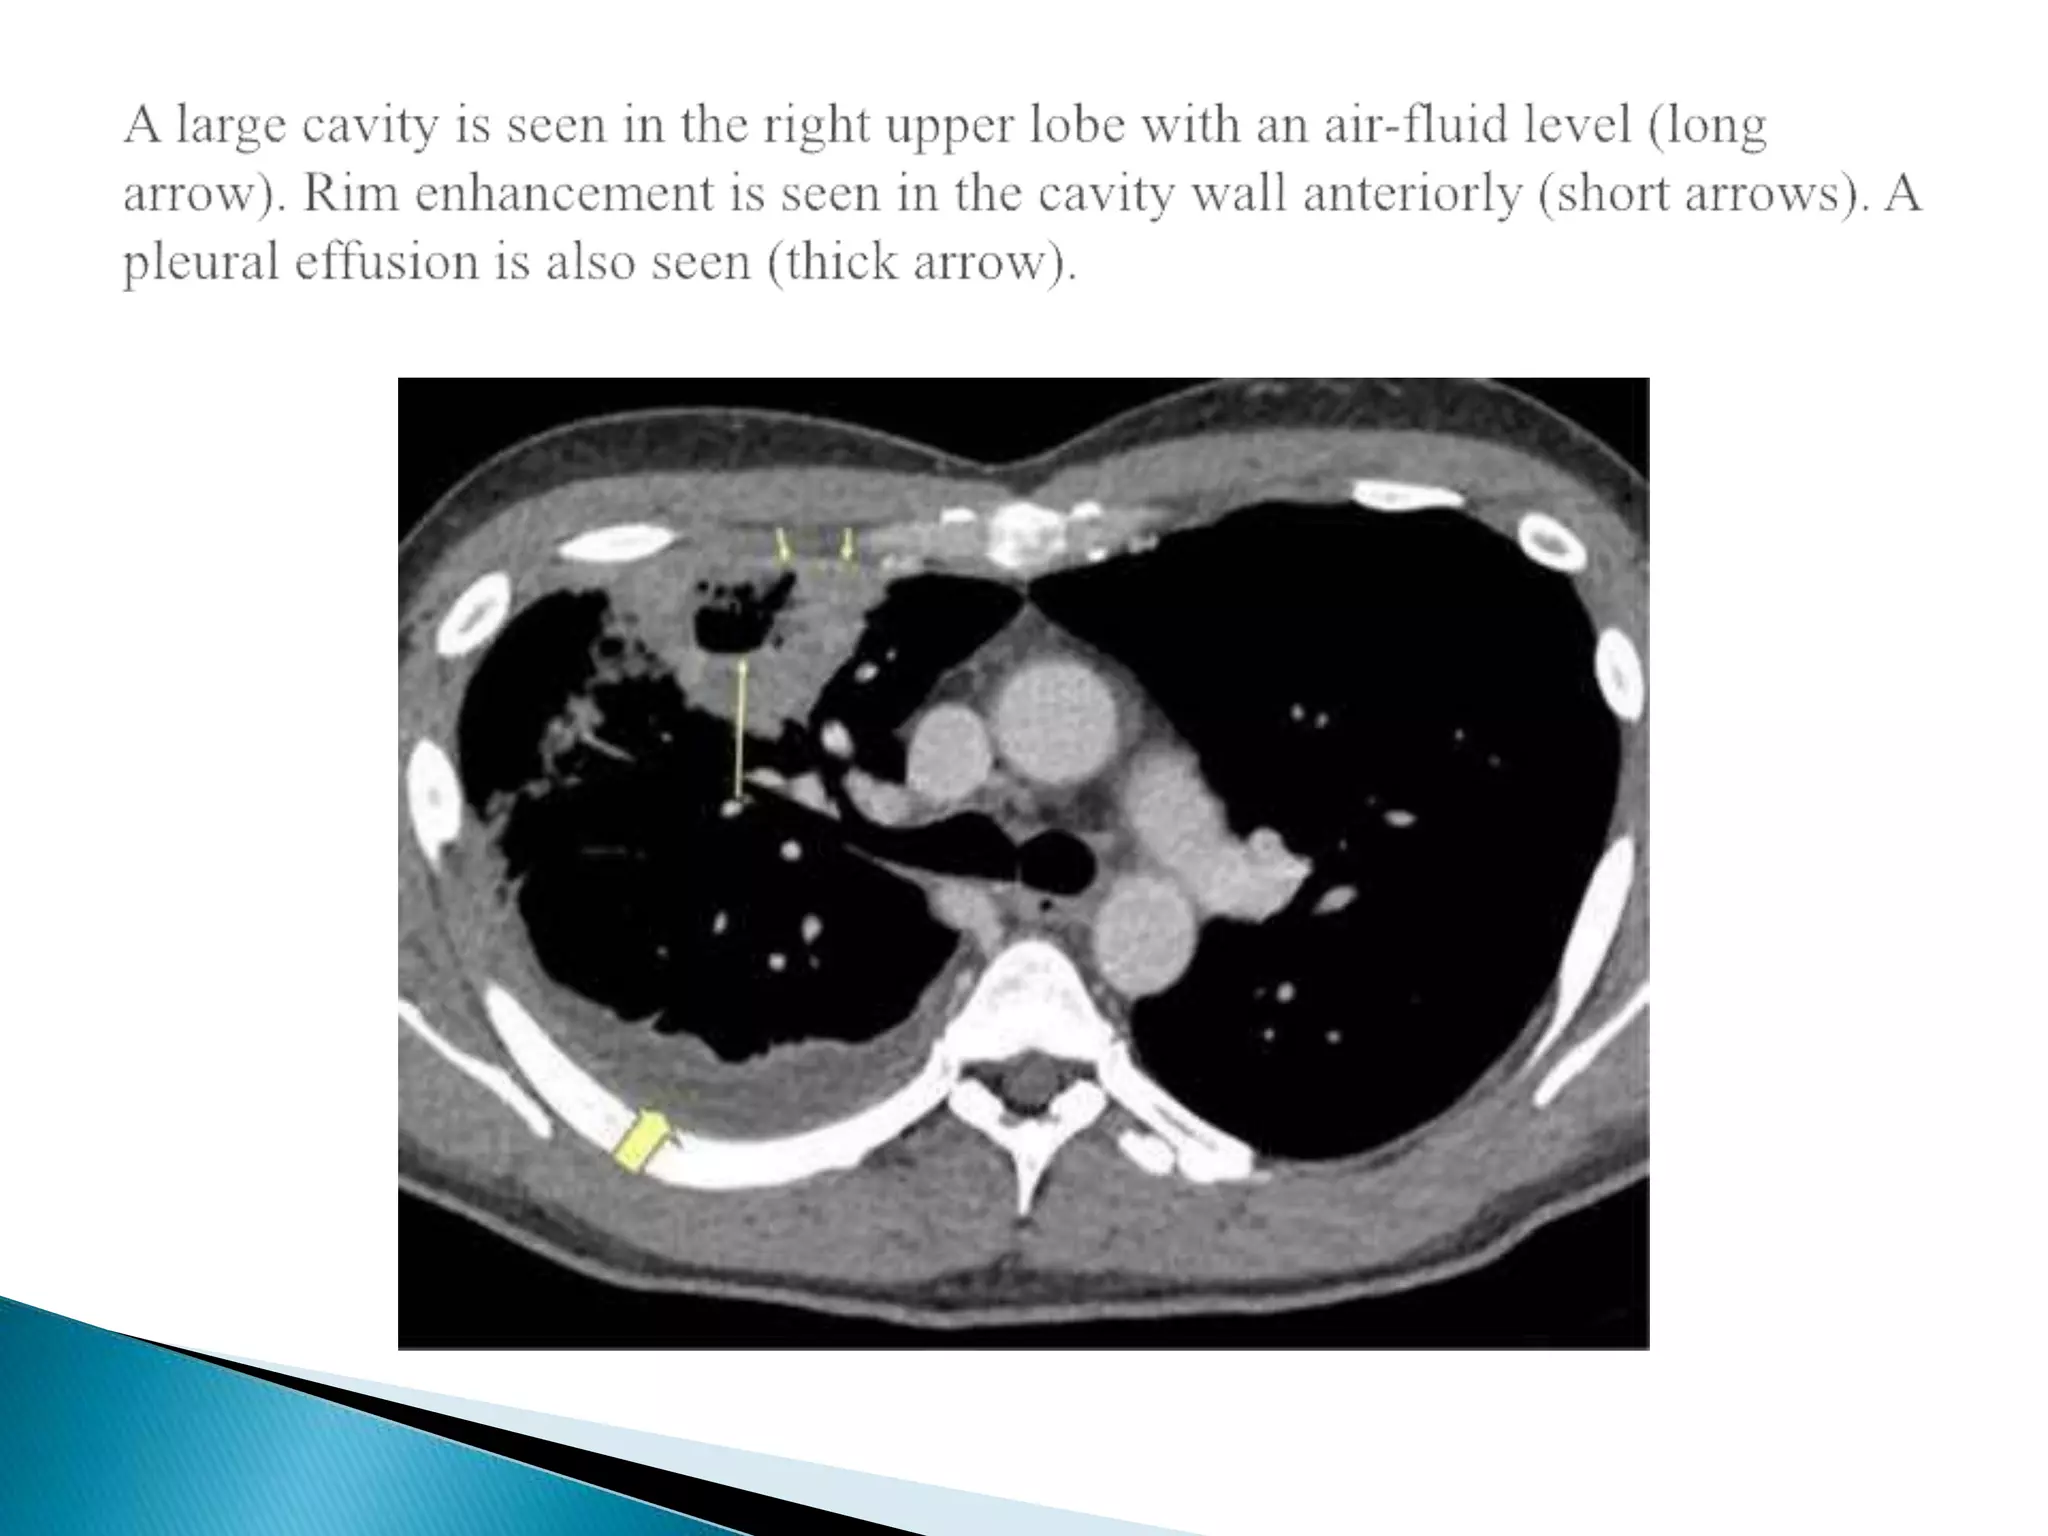

Chest radiograph showing cavitary lesion in the right upper lung lobe